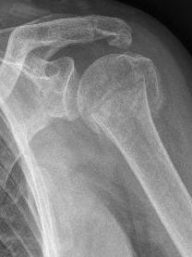

Picture: Here is a subcapital upper arm break in a young woman. An angle stable plate osteosynthesis was performed to stabilize the head in correct position to the humeral shaft and shoulder joint. Especially in young patients, We strive to treat non-invasively and as gently as possible. This possibility is often due to the bone quality in young as opposed to older people.